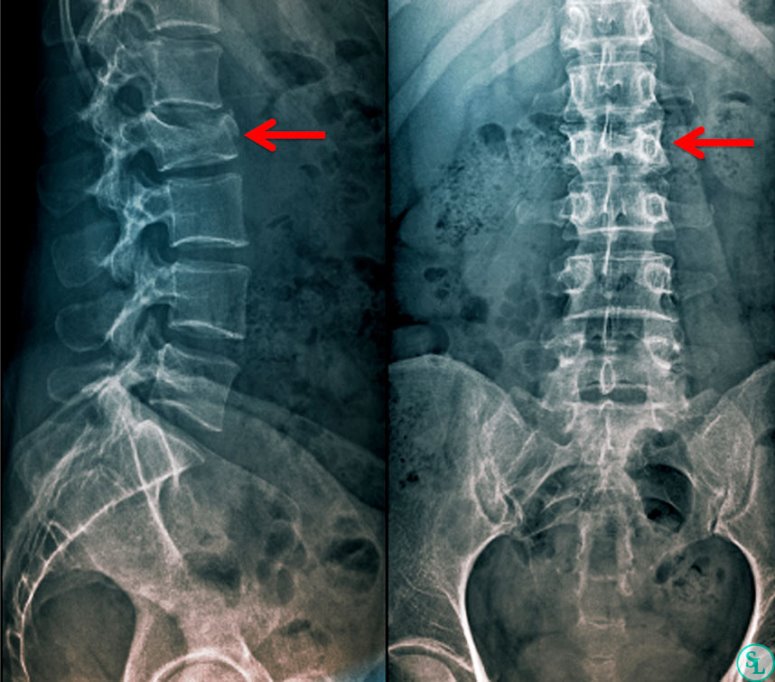

Наиболее частыми причинами травм позвоночника являются дорожно-транспортные происшествия, падения с высоты, спортивные травмы или прямые удары в область спины или шеи. Вне зависимости от механизма, основным и наиболее очевидным симптомом является острая боль в области повреждения — шее, грудном или поясничном отделе. Эта боль может быть локализованной или отдавать в конечности, грудь или живот. Усиление боли при малейшем движении или попытке изменить положение тела – очень тревожный знак. Пострадавший часто инстинктивно избегает движения, пытаясь зафиксировать повреждённую область. Иногда боль может быть отсутствовать или быть слабо выраженной, особенно если произошёл шок или повреждение спинного мозга.

- Деформация или отёк: Видимое изменение контура позвоночника (искривление, горб) или значительный отёк и гематома в месте удара.